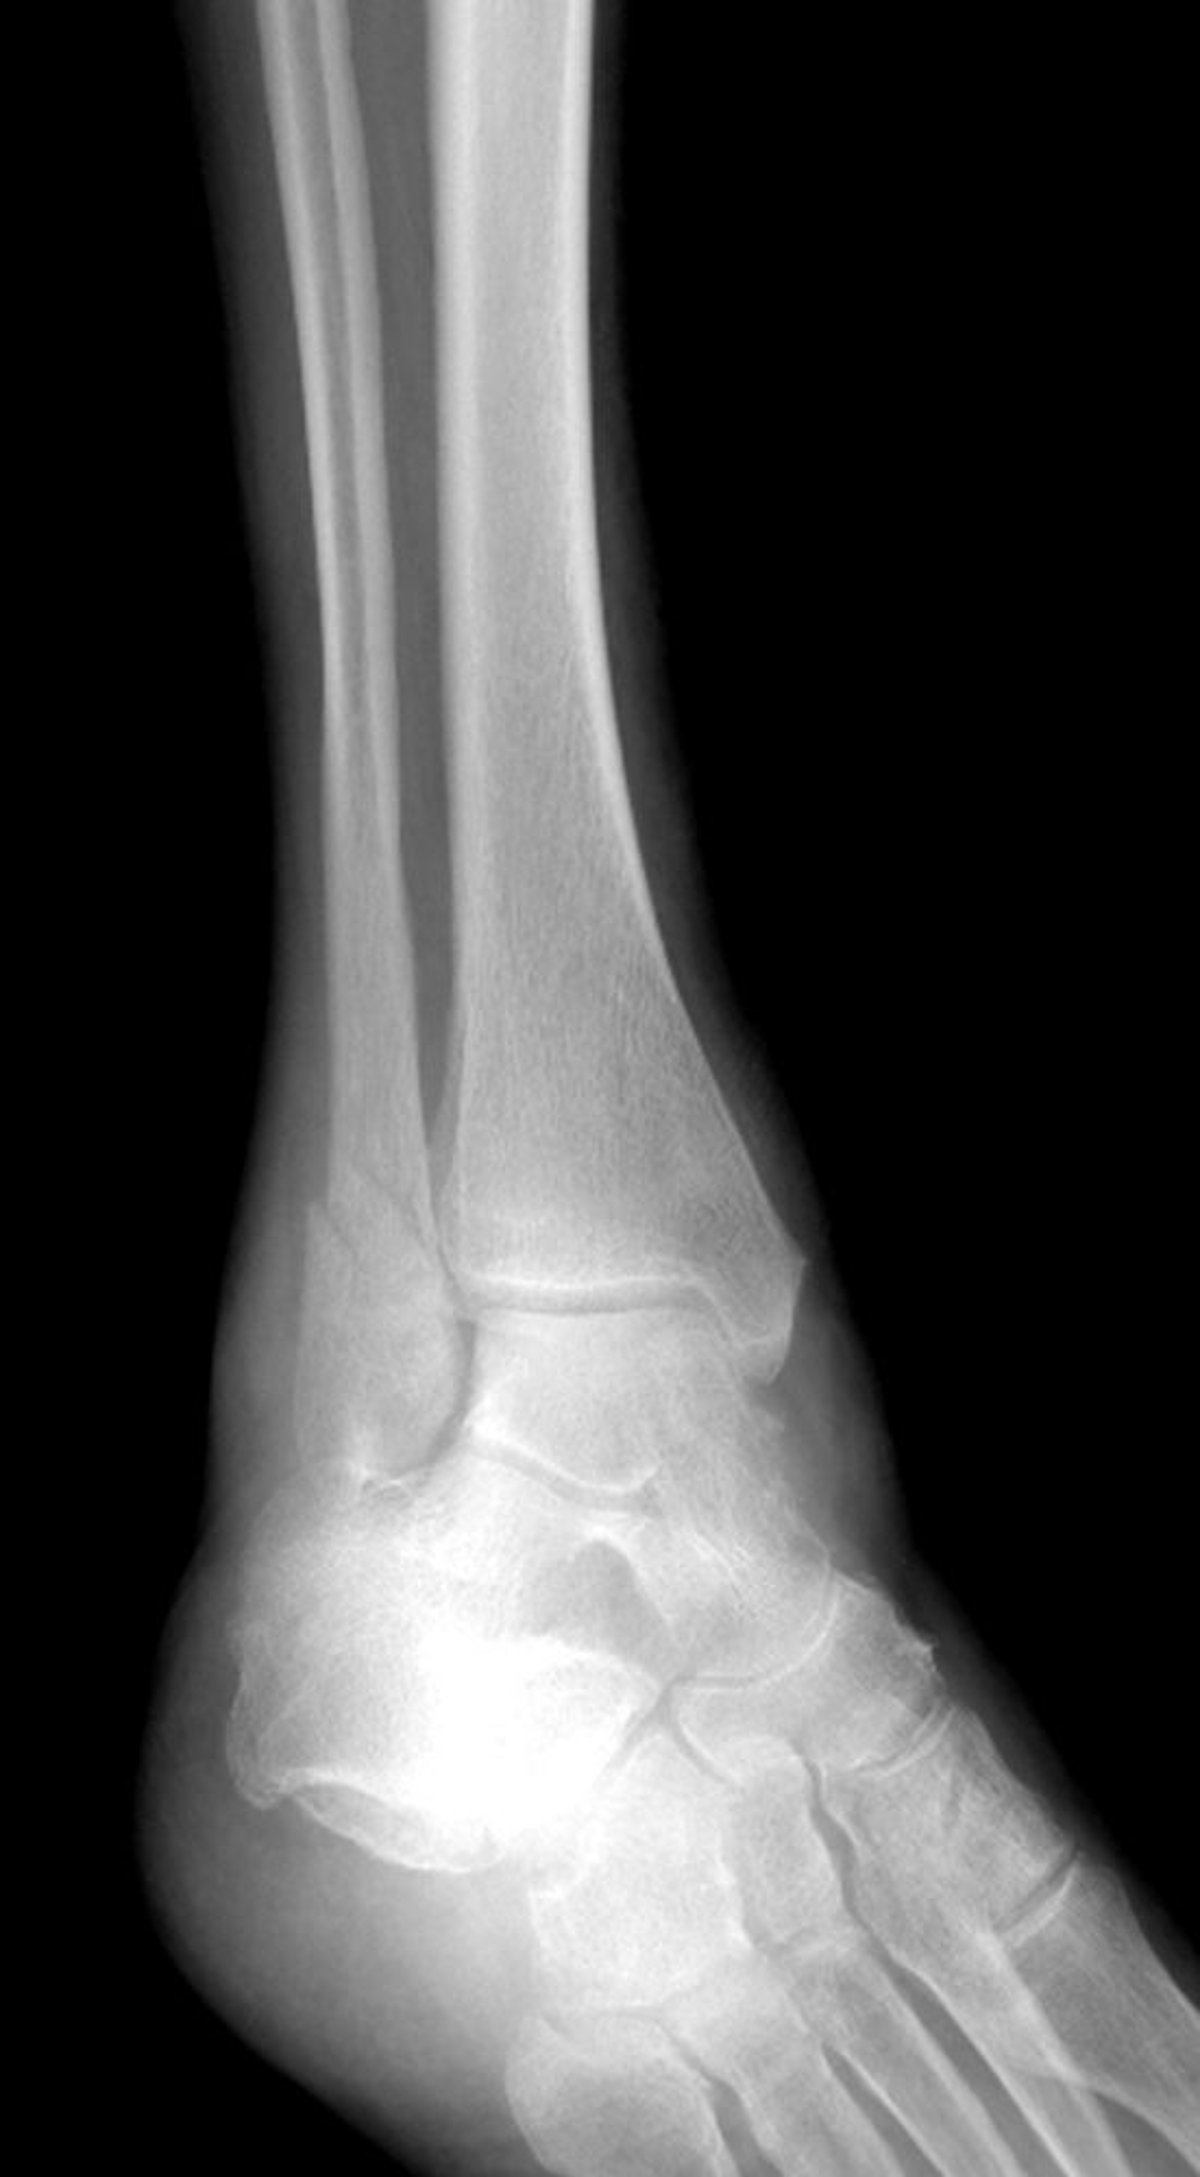

Fratura do maléolo lateral

Essa fratura do tornozelo afeta o maléolo lateral, mas poupa o maléolo medial.